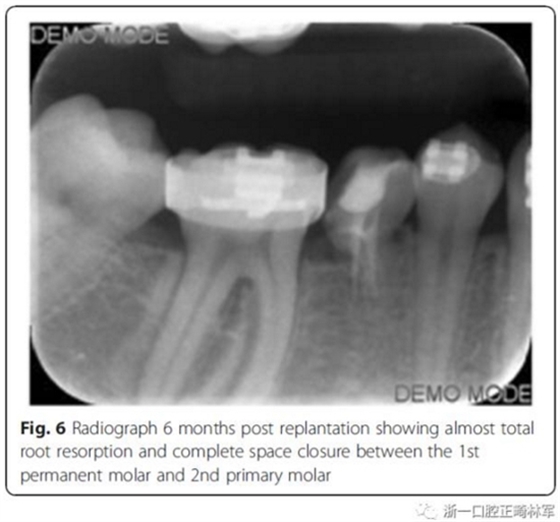

第6個月,臨床和影像檢查顯示乳牙幾近完全的替代性牙根吸收和間隙的完全關(guān)閉。最終,將乳磨牙拔除并開始進行完整的正畸治療。在接下來一年,用0.017’’*0.025’’末端回彎的不銹鋼弓絲和彈性牽引剩余間隙關(guān)閉,并以II類牽引作為支持。